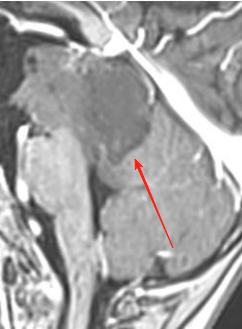

2025年复查发现,肿瘤已增长至4.0×2.8×3.1cm,占据中脑背侧及脑桥上段,覆盖整个松果体区、压迫小脑、侵袭双侧丘脑。面对如此危急的情况,巴教授明确指出:“继续观察只会放任肿瘤继续进展——若体积超出临界值将不再具备手术条件!因此延长观察期属重大决策失误。”